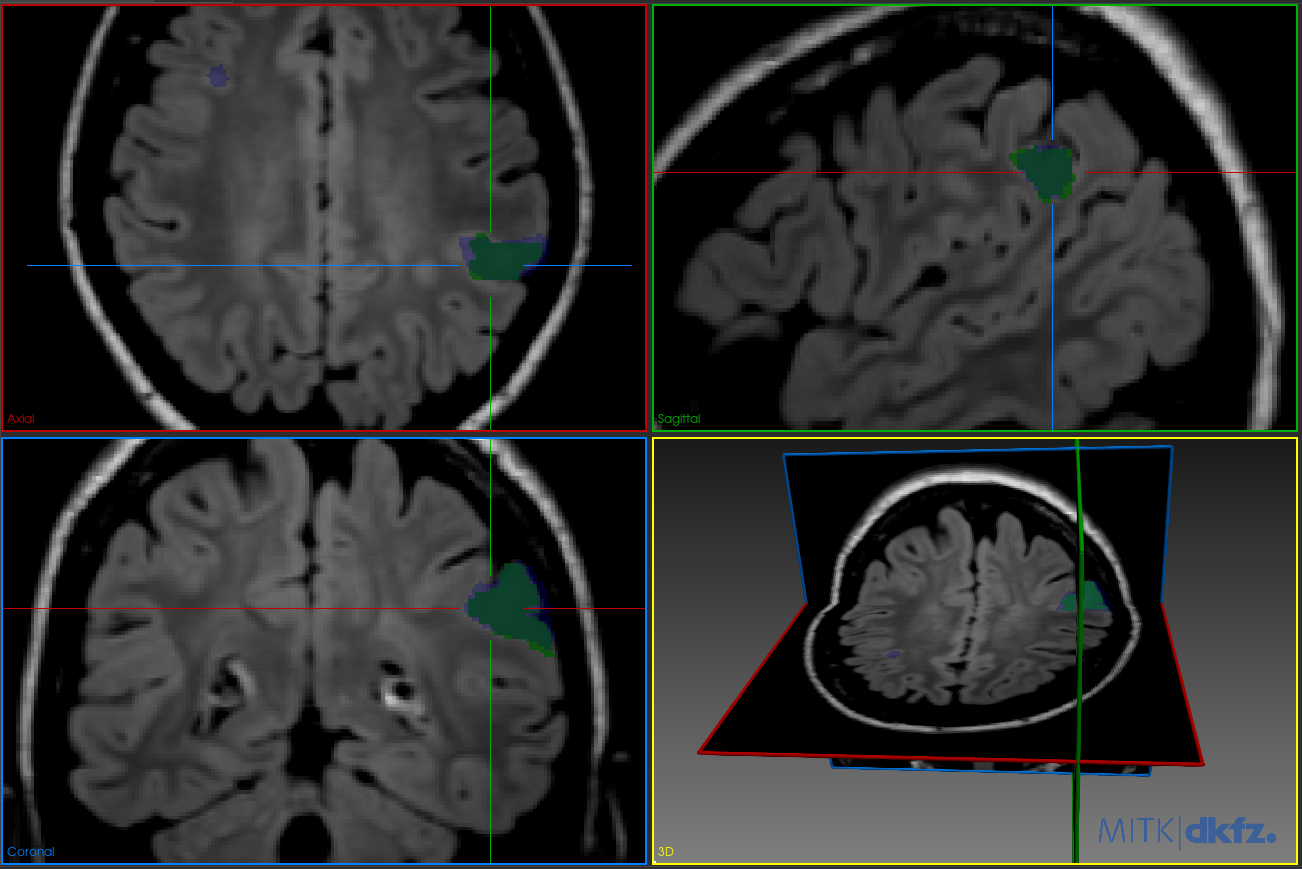

Figure 3 illustrates the segmentation results when the model is trained with the proposed TV loss added to Dice loss. In Figure 3(a), the predicted mask (blue) shows a high degree of overlap with the ground truth (green) and no visible false positives, even without post-processing. This highlights the regularizing effect of TV loss in enforcing spatial smoothness during training. In Figure 3(b), the result after post-processing (yellow mask) is nearly identical to the unprocessed prediction, confirming that TV loss had already smoothed the prediction to the extent that additional post-processing has minimal impact.

Refer to caption

(a) Model trained with TV loss. Green: ground truth mask; blue: predicted mask. The false positives are no longer present.

(b) Model trained with TV loss after post-processing. Green: ground truth mask; yellow: predicted mask. Minimal change, indicating TV loss already enforced spatial consistency.

Figure 3: Segmentation results with the proposed TV loss, before and after post-processing.